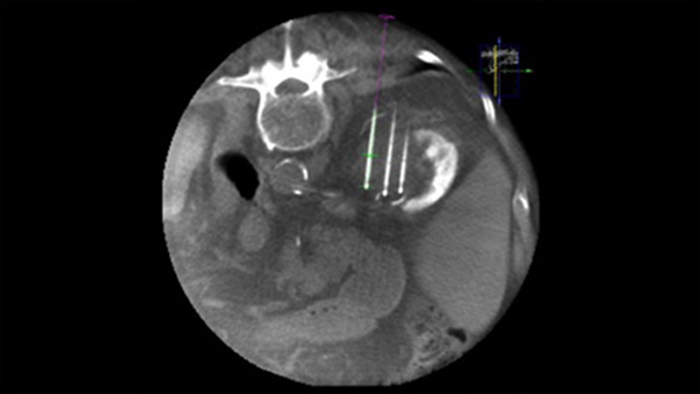

A ablação percutânea (radiofrequência, micro-ondas e crioablação) é um tratamento minimamente invasivo e bem estabelecido dos tumores renais, hepáticos, pulmonares e ósseos. É fundamental definir os limites do tumor e decidir sobre um número ideal de agulhas e a trajetória da agulha correspondente para poder realizar um tratamento tumoral completo e não causar danos no tecido circundante. Navegar com precisão a uma dose baixa para a lesão de interesse sem reposicionamento da agulha aumenta a oportunidade de sucesso e reduz o risco de complicações das biopsias ou ablações. A confirmação do ponto final do tratamento de ablação pode ser realizada com imagens 3D enquanto o paciente ainda está na mesa.

O SmartCT SoftTissue oferece uma técnica de aquisição de TT de feixe cónico (CBCT) aumentada com orientação passo a passo, visualização 3D avançada e ferramentas de medição, tudo isto acessível no módulo de ecrã tátil ao lado da mesa.